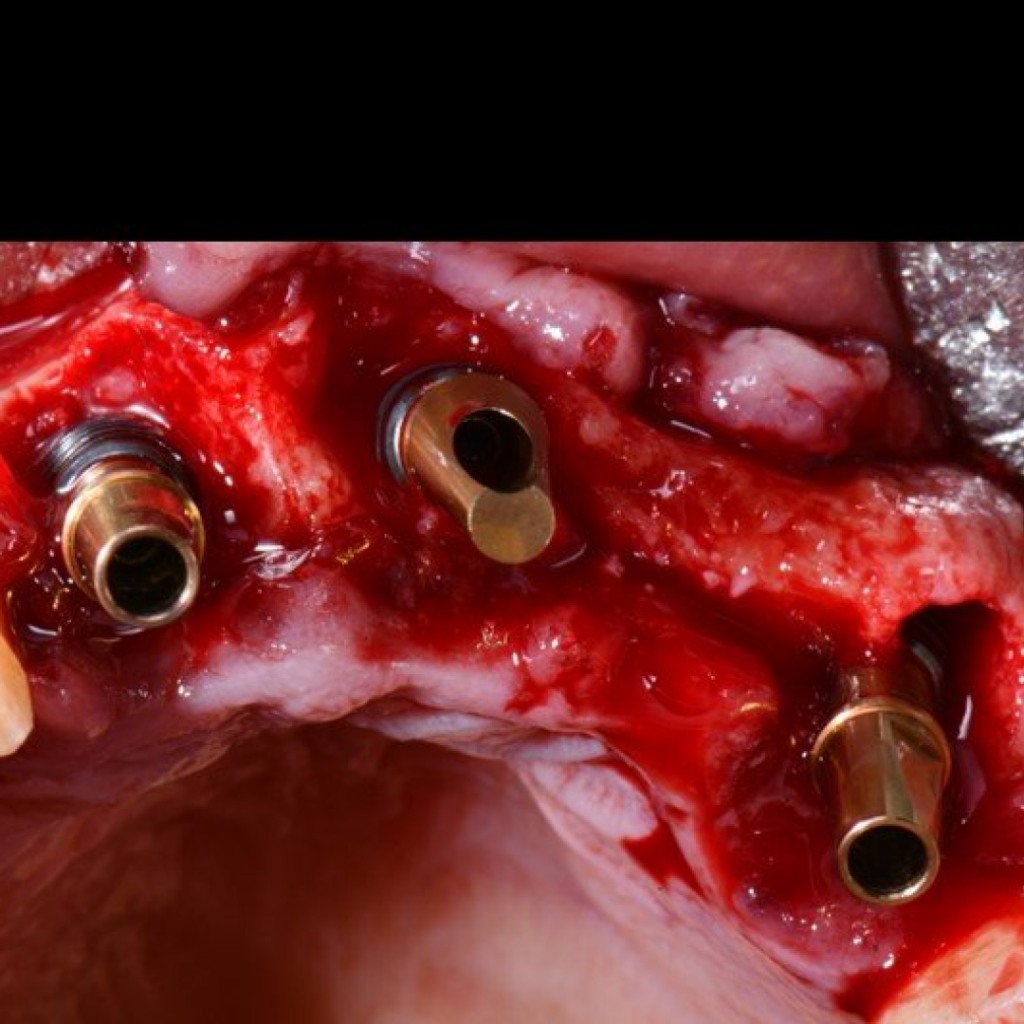

- Проведение имплантации AnyRidge с немедленной нагрузкой

- Заполнение костных дефектов смесью из костного материала TI-oss, аутокости пациента и обогащенной тромбоцитами плазмой PRP

- Установка абатментов для временного протеза